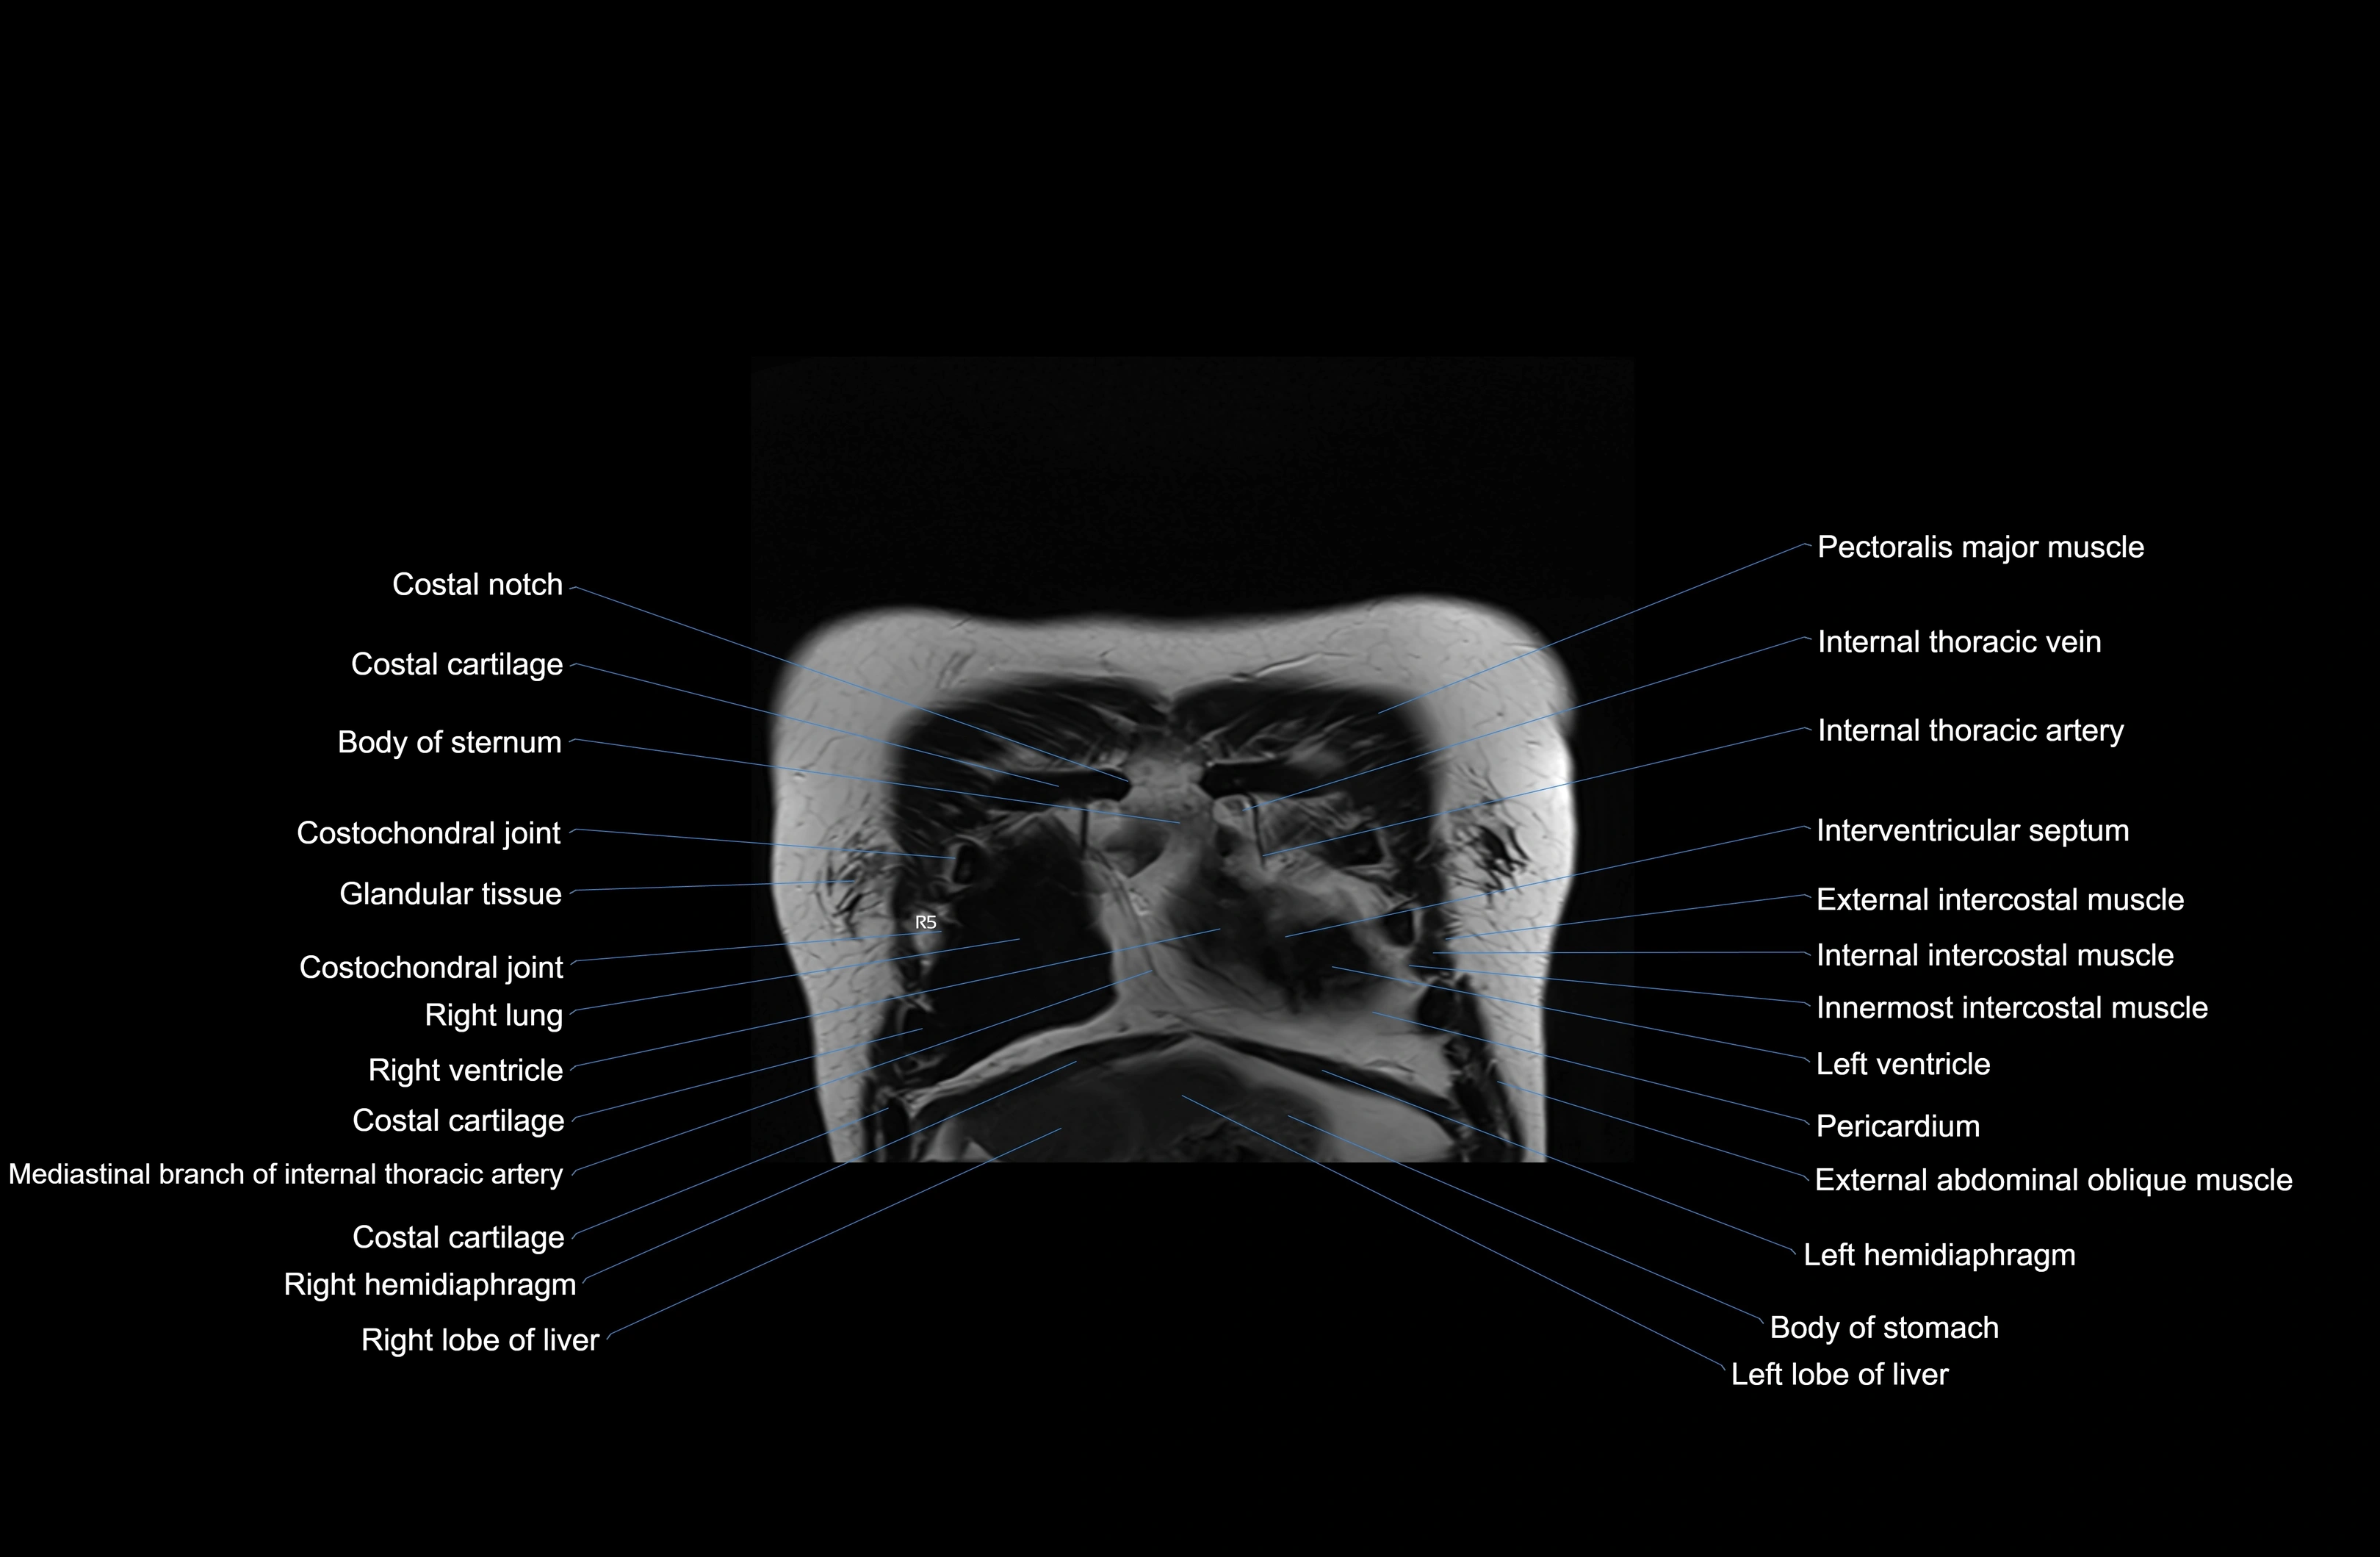

- Body of sternum

- Costal cartilages

- Costal notches

- Costochondral joints

- Intercostal muscles

- Internal thoracic artery

- Internal thoracic veins

- Interventricular Septum

- Left ventricle

- Pericardium

- Right hemidiaphragm

- Right lobe of liver

- Right ventricle